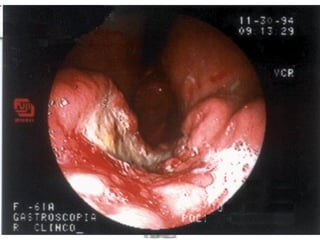

2. ENDOSCOPIA

• Simplemente para

descartar las causas

secundaria de la

acalasia

• Hasta en el 40%:

Normal